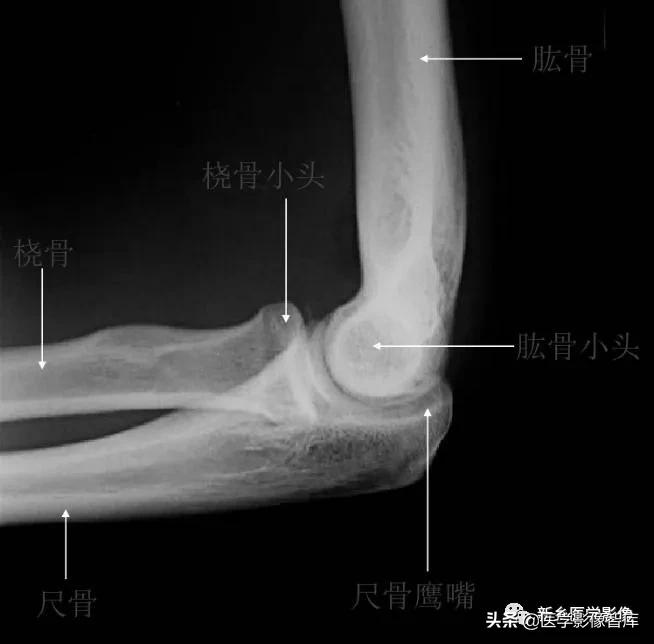

肘关节的X线解剖肘关节常规X线片包括伸肘前后位及屈肘90°的侧位(图1)。正位像肱桡关节间隙清晰,呈下凹的浅弧形;肱尺关节间隙有尺骨滑车切迹重叠而变暗,呈上凹的弧形,故而正位片上肘关节间隙呈波浪状。屈肘侧位片,肱尺关节间隙清晰,呈半环形,前为冠突,后为鹰嘴。肱桡关节掌侧清晰,背侧部分和尺骨冠突相重叠。此时通过桡骨纵轴线的延长线也穿过肱骨小头中心。